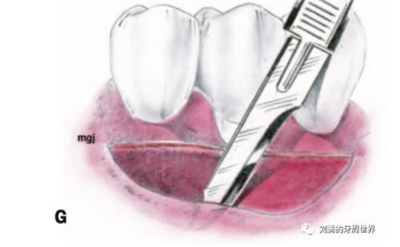

3、用15號刀片,在受區(qū)膜齦聯(lián)合的位置從遠(yuǎn)中向近中做半厚切口,刀片平行于骨面(E和F)

4、刀片按照受區(qū)的近遠(yuǎn)中長度完成初始的半厚瓣全長切口